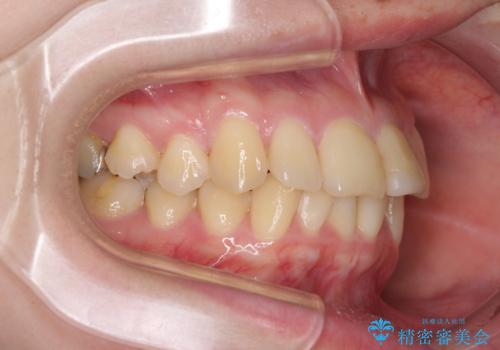

上下前歯のデコボコをきれいに インビザラインによる矯正治療

- 前歯の著しい叢生と前突感を気にして来院された患者様です。

叢生が強いため、事前に前歯をワイヤー矯正で速やかに叢生を解消し、その後はインビザラインにて矯正治療を行うこととしました。

ワイヤー矯正を併用したことで前歯の叢生を速やかに解消することができました。

一方口元の突出感を改善するために時間がかかり、2年超を要しましたが、満足のいく仕上がりとなりました。